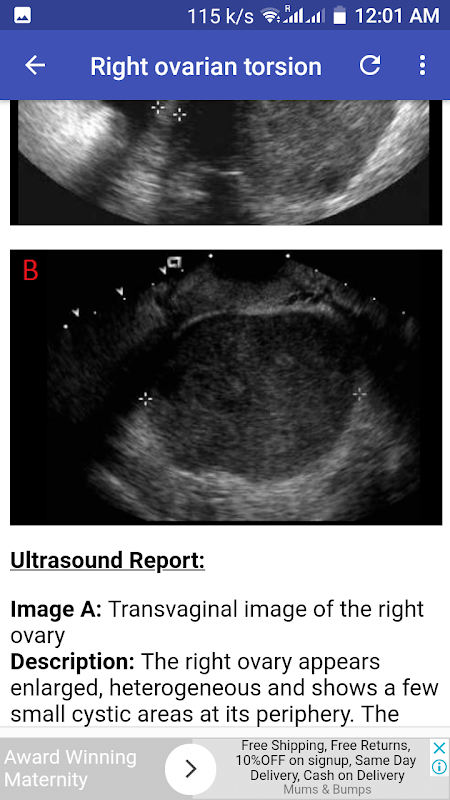

Torsione ovarica destra